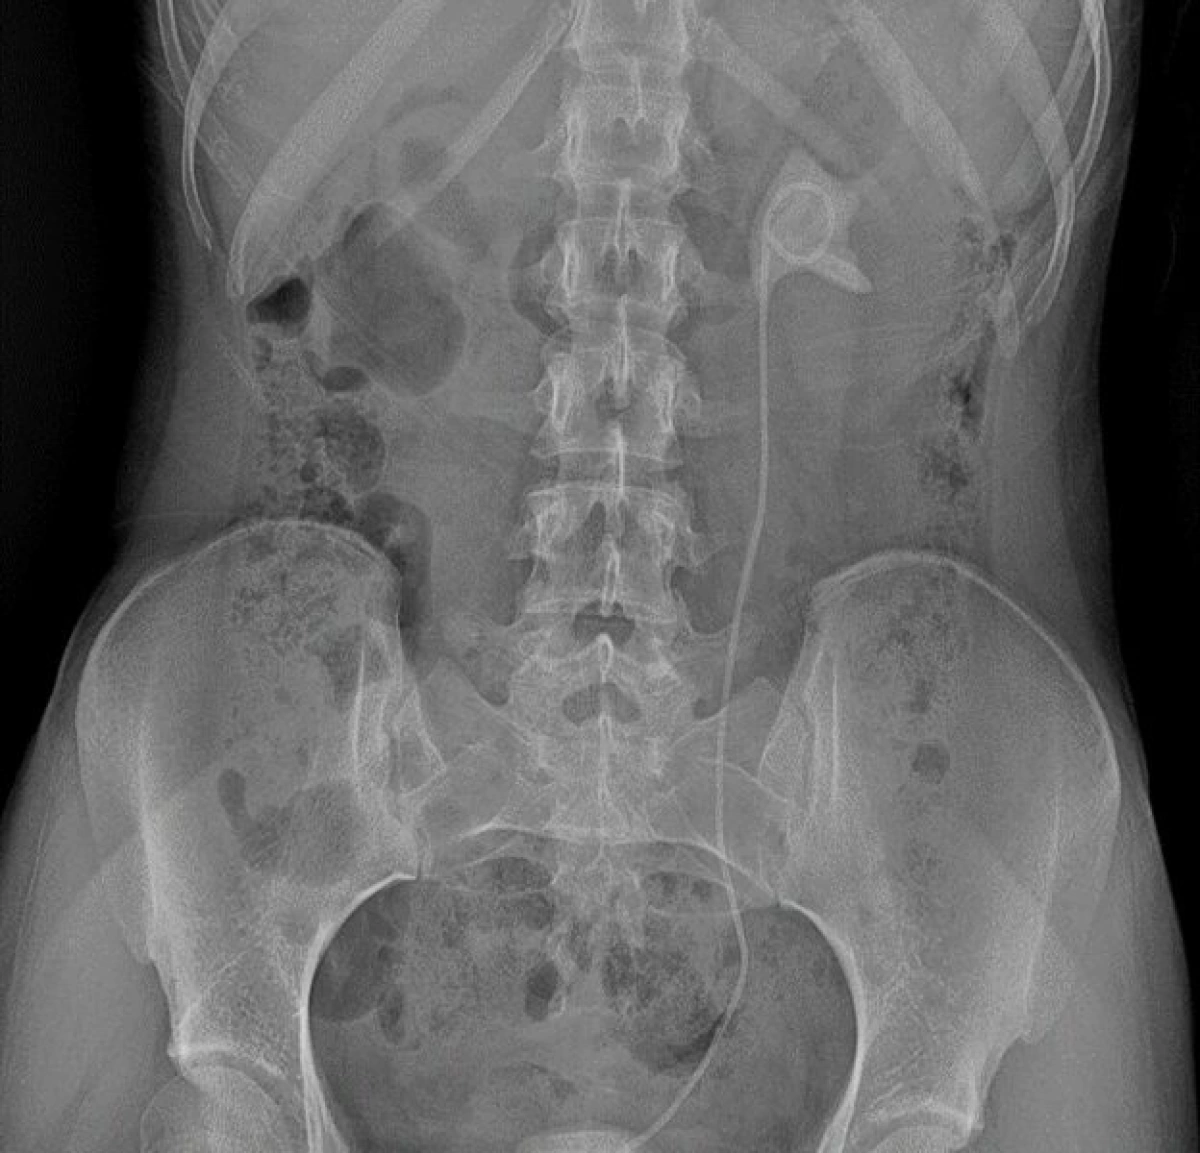

Непростой, но успешный курс лечения юной больной завершился во втором урологическом отделении клинической больницы №9. Девушка поступила сюда с серьёзным комплексом осложнений. В другой больнице в связи с некупируемой почечной коликой ей был установлен мочеточниковый стент. Однако в установленный срок через 6 недель после операции пациентка не пришла для его удаления и в дальнейшем у врачей не наблюдалась. В результате стент оставался в организме целых 6 месяцев, как следствие — произошло отложение солей и формирование камней в мочевом пузыре и почке. Такое сочетание значительно усложнило клиническую картину и потребовало комплексного подхода к лечению. Девушке требовалась операция. На помощь пришла команда талантливых урологов клинической больницы №9. С помощью новейшего оборудования они провели две высокотехнологичные операции.

Первая операция — контактная цистолитотрипсия с использованием гольмиевого лазера. Этот метод позволил с высокой точностью раздробить камень в мочевом пузыре, минимизировать повреждение тканей и одновременно проработать область, затронутую длительным нахождением стента.

Вторая операция была также выполнена с помощью гольмиевого лазера для безопасного удаления стента, устранения последствий его длительного нахождения в организме, работы с камнем в почке — дробление и удаление.